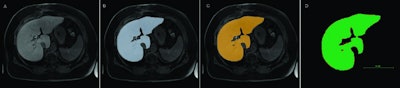

The graphic shows the segmentations of an MRI scan (A) with the manual (B) and the automatic variant (C). Panel D illustrates the comparison between manual and fully automatic segmentation. The green pixels indicate the areas of concordance, while the red pixels represent the areas of deviation. Image courtesy of Dr. Niklas Verloh.Many of these 3D analyses require segmentation of the organs. Organs are subdivided into individual anatomical or functional sections to provide the requesting physician with the desired information. This segmentation takes a lot of time if the radiologist has to manually do it. However, CT software programs are now available, which can at least partially automate segmentation.